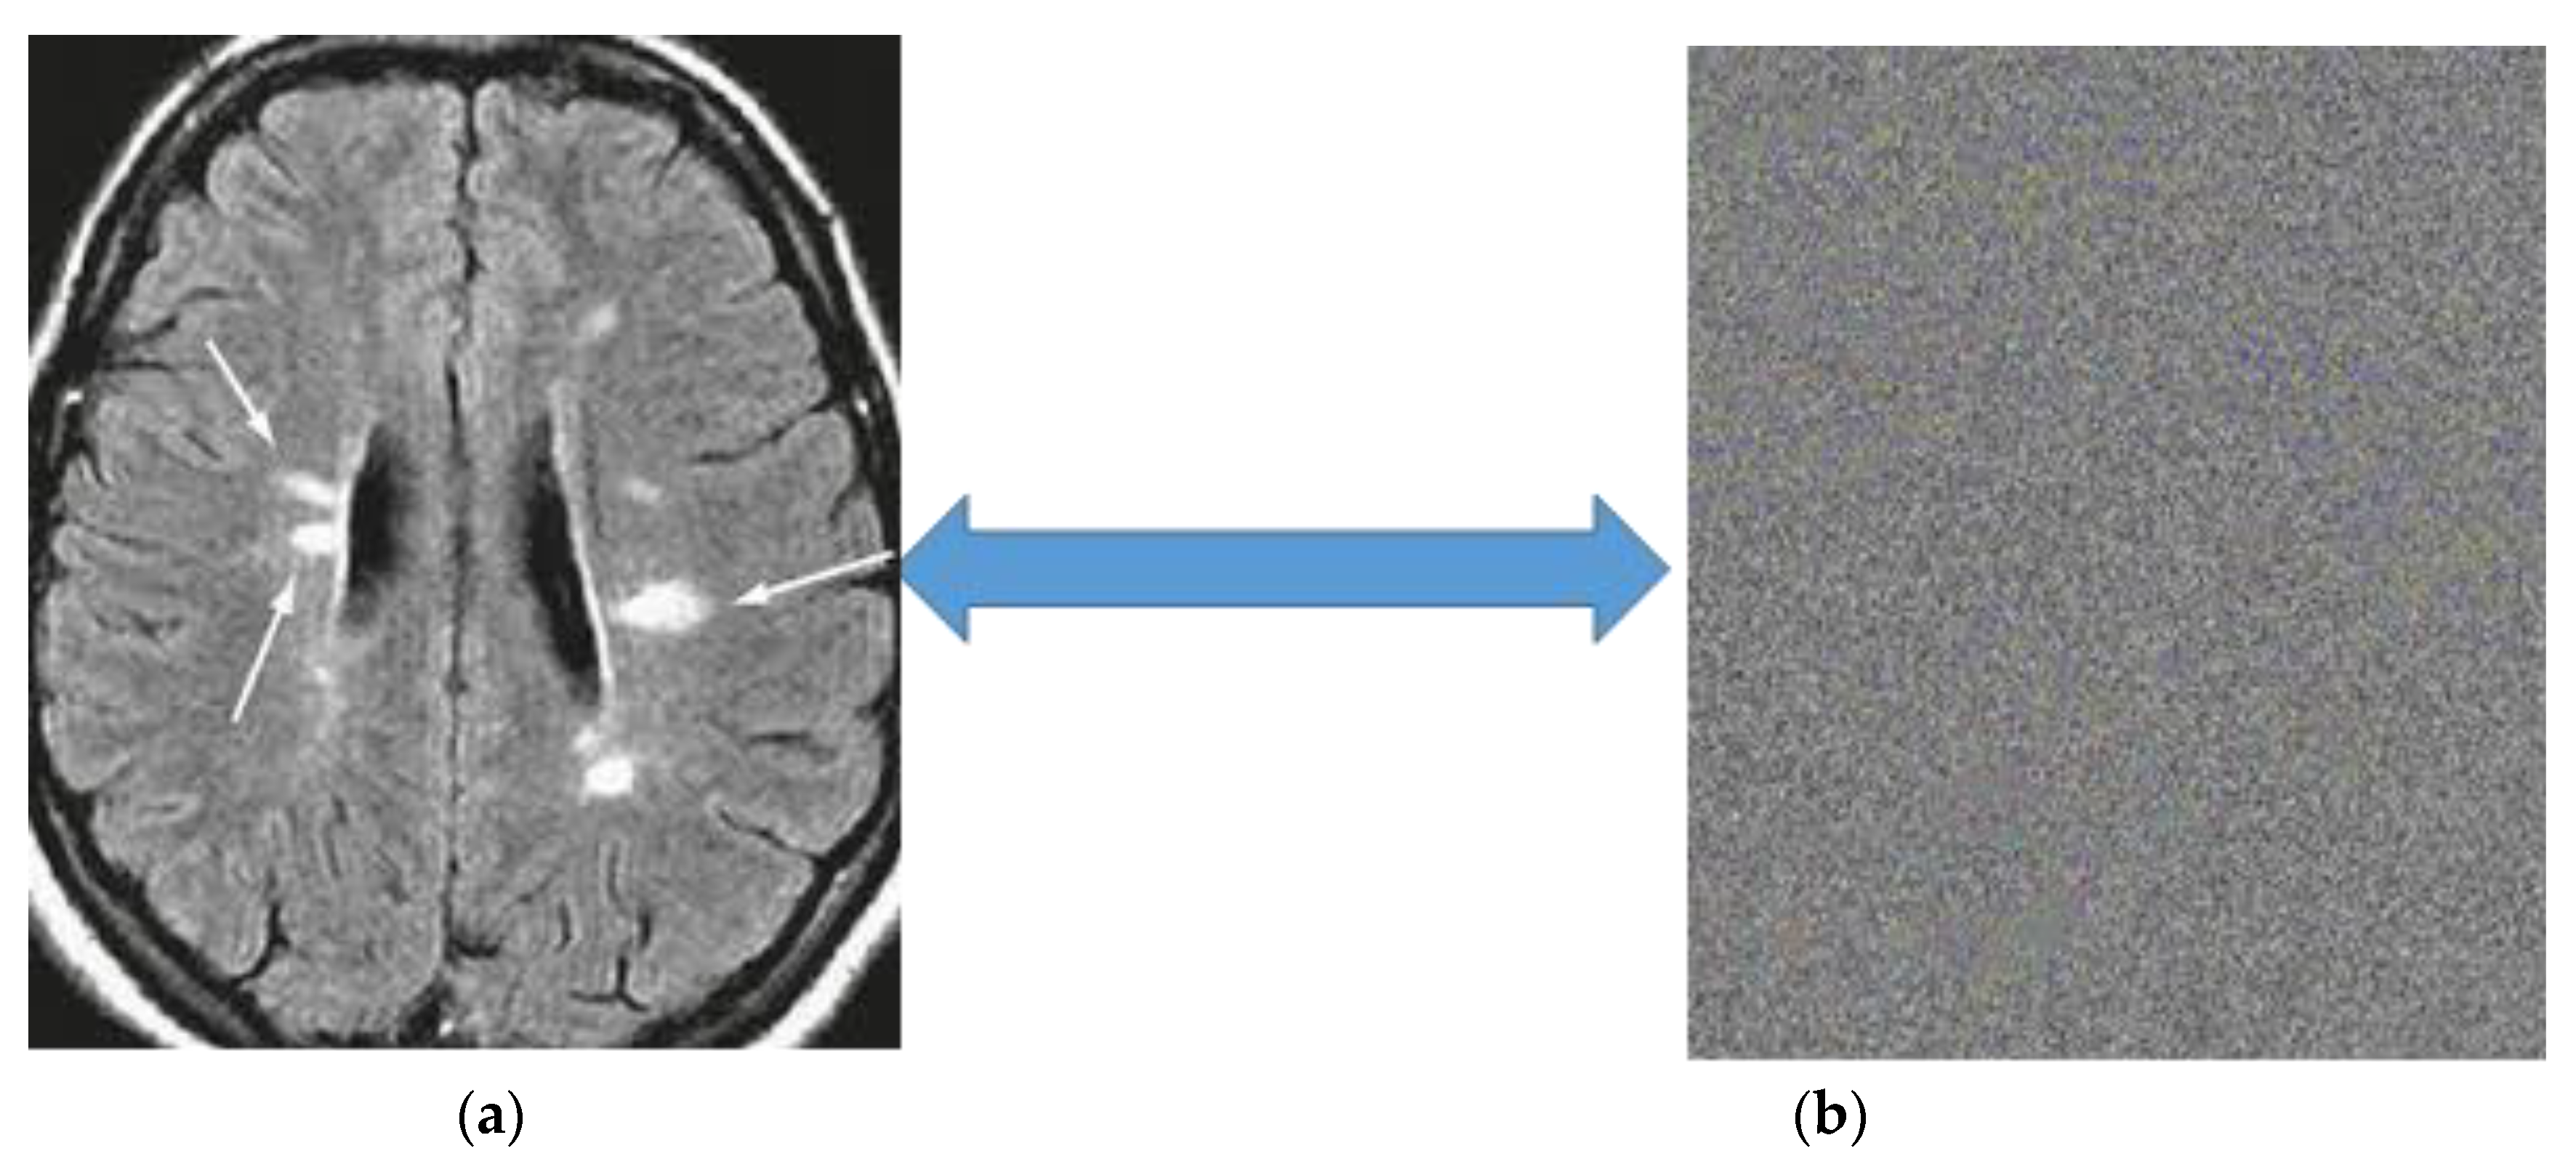

- Convolutional Layer: A convolutional layer is a series of small parameterized filters that operate on the input data domain. In this study, inputs are raw brain images and encrypted brain images data. The aim of the convolutional layers is to learn abstract features from the data [45]. Every filter is an n × n matrix called a stride. In this case, we have n = 3. We convolve the pixels in the input image and evaluate the dot product, called feature maps, of the filter values and related values in the pixel neighbour. For example, the stride is a pair of numbers (3,3), in which, in each step, we slide a three-unit filter to the left or down. In summary, given a brain MRI image I (Figure 1), consisting of R rows, C columns, and D layers, a 2D function I (x, y, z) where 0 ≤ x < R, 0 ≤ y < C, and 0 ≤ z < D are spatial coordinates, amplitude I is called the intensity at any point on the 2D set with coordinates (x, y, z) [46]. The process of extracting feature maps is defined in Equation (1):where If is the convolved image, and Wi,j,k are coefficients of kernels or strides for convolving 2D arrays.